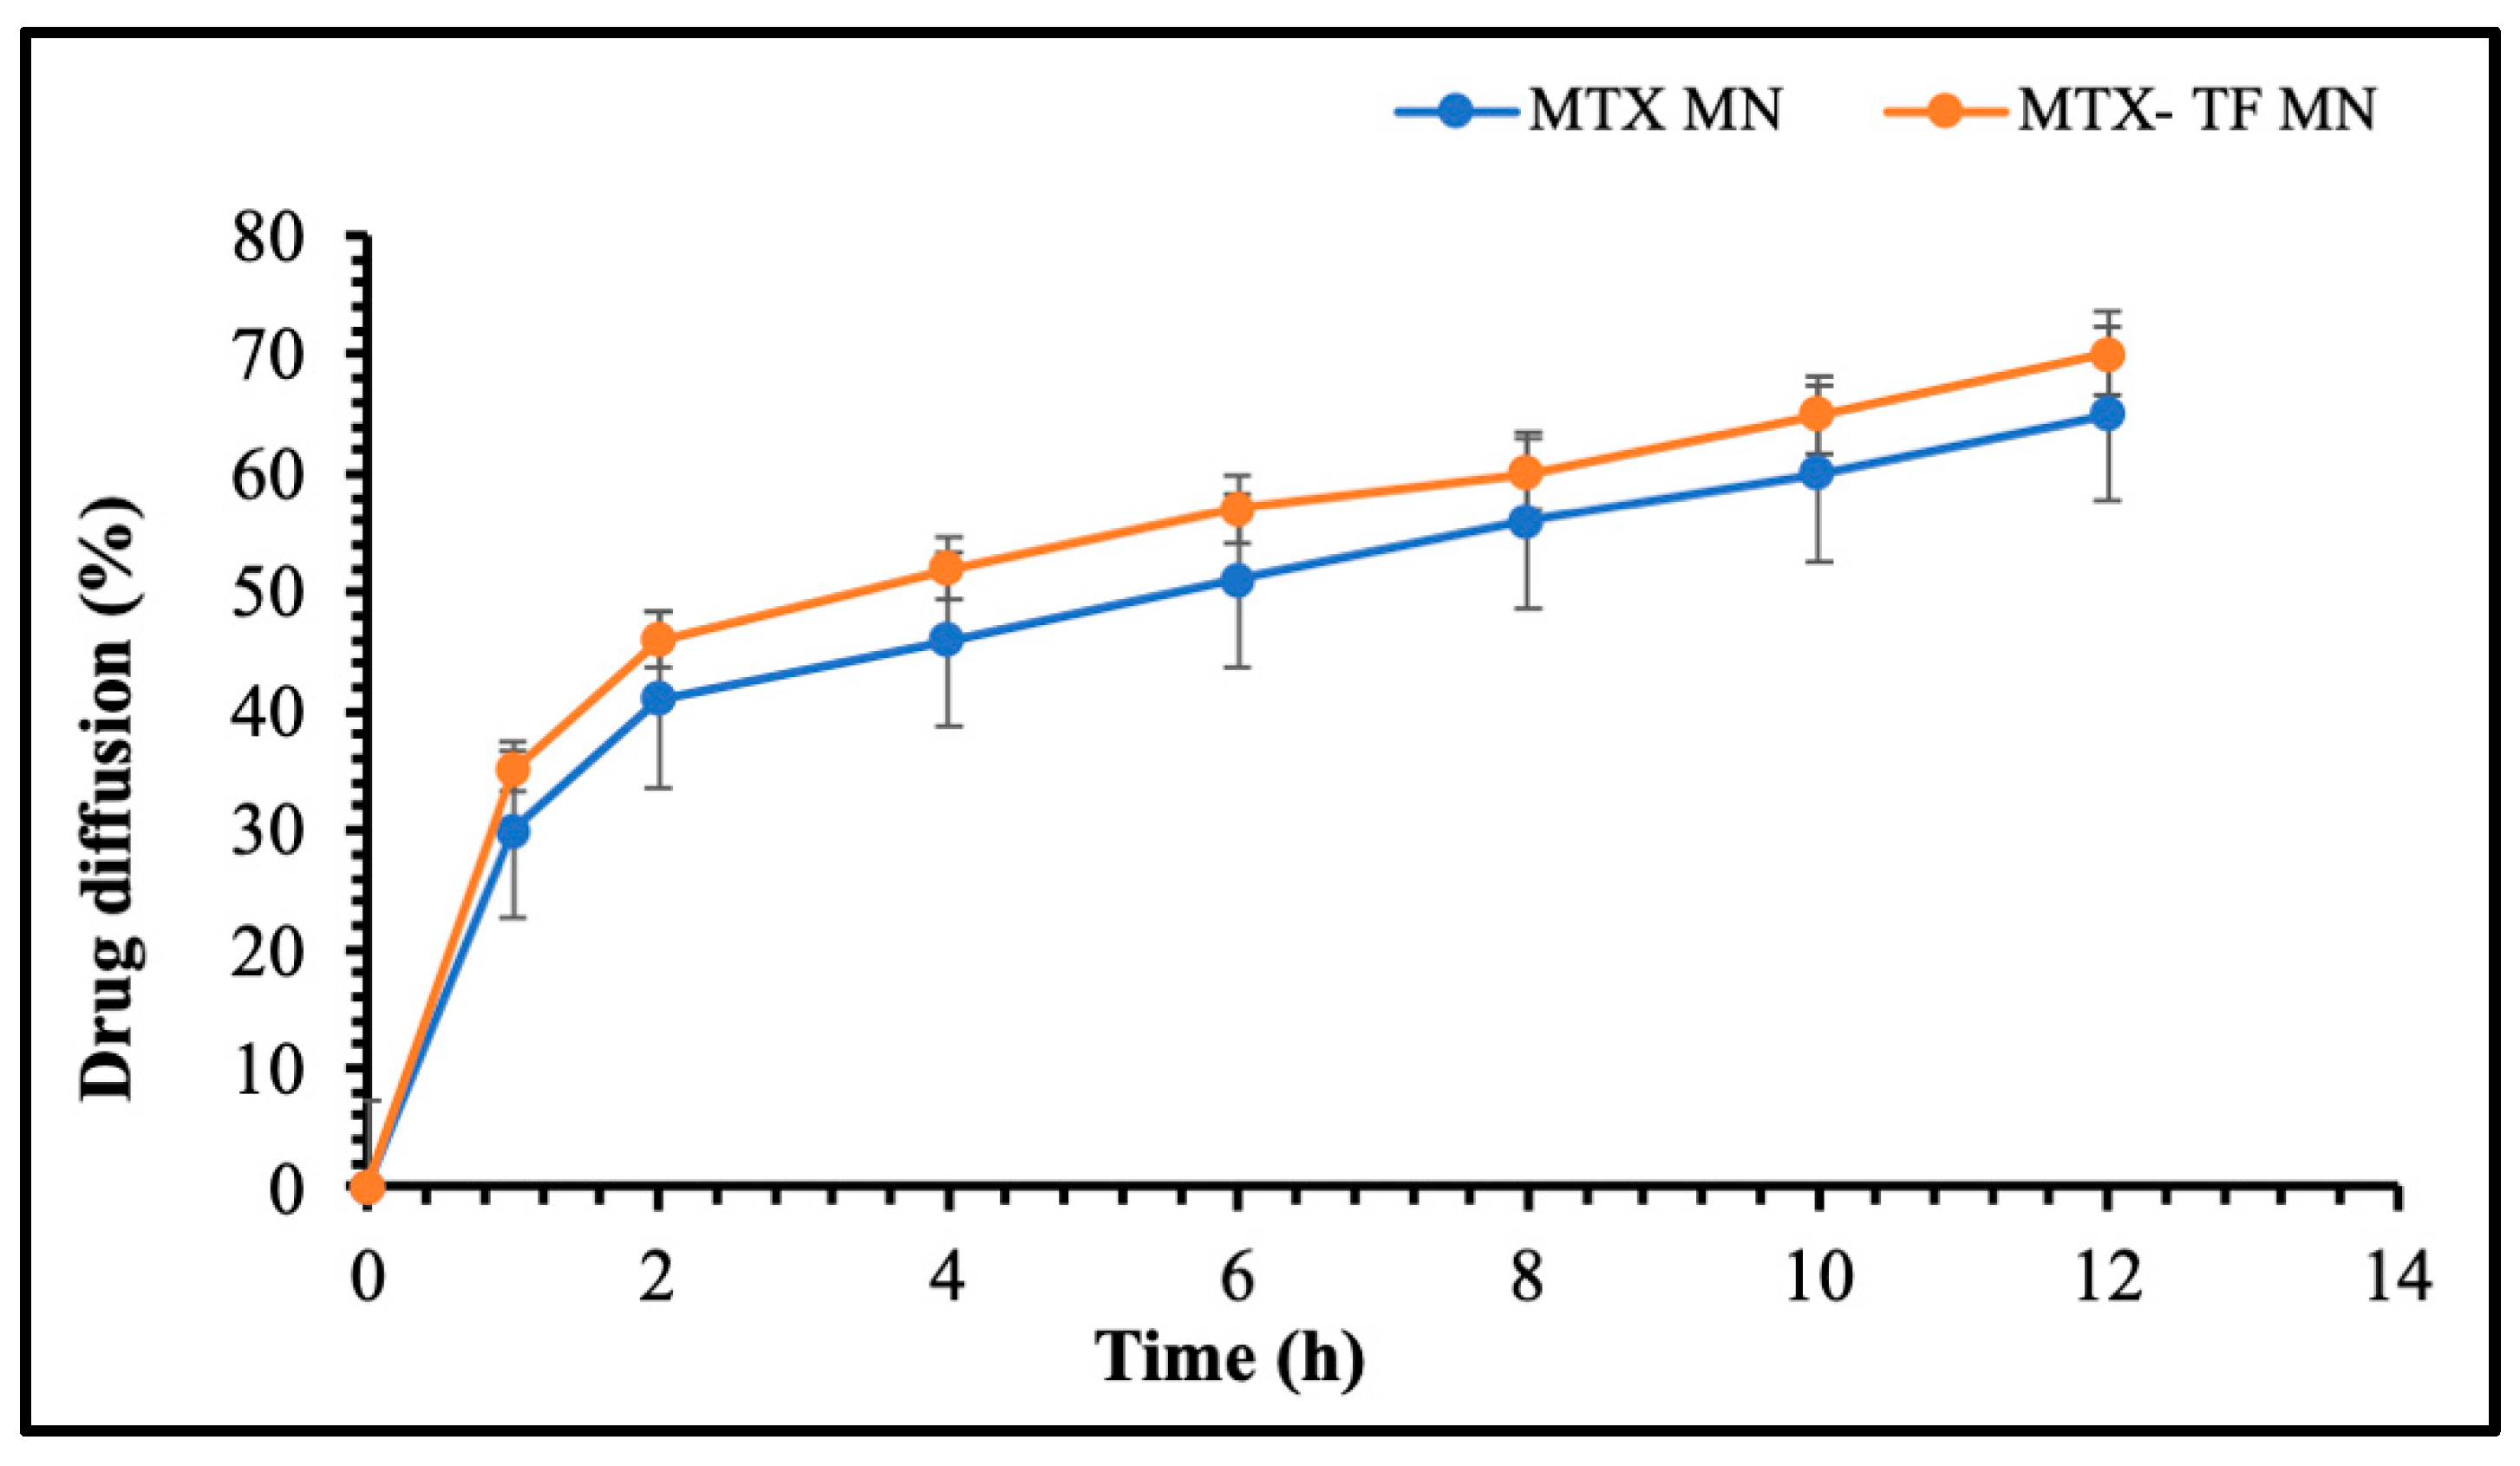

2.6.3. In Vitro Release Study of MTX-MN and MTX-TF-MN

3.4.3. In Vitro Release Assay for MTX-MN and MTXTF-MN